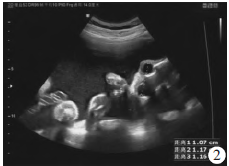

胎儿左眼距1.2 cm,右眼距1.2 cm,眼距1 cm(图2)。胎儿上唇中部唇腭回声缺失约0.9 cm(图3)。胎儿双肺显示不清,部分肝脏进入左侧胸腔,右移(图4)。胎儿右侧足底平面和小腿骨骼长轴切面可在同一切面内显示,右侧拇趾短与第2趾间距增大(图5)。超声诊断:①单胎,中孕,存活儿;②胎儿全前脑畸形;③胎儿全前脑面容(正中唇腭裂、眼距过近);④胎儿右足内翻合并拇趾短、草鞋脚;⑤胎儿左侧膈疝;⑥脐带胎盘入口处囊肿;⑦羊水过多。

图2胎儿双眼超声表现